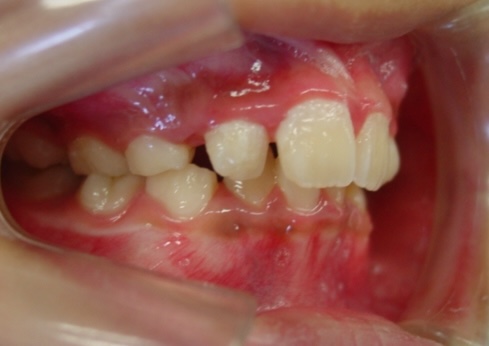

症例1-②

そして、永久歯がすべて生えそろって症例1-②の写真のようになります。上は、軽度の八重歯です。この程度の八重歯は永久歯を抜くことなく治療可能ですが、問題は右下の4番がスペースがまったく無いということです。ここで、一般的な矯正では、右下4番の小臼歯の抜歯と、それに伴う、その他3本の小臼歯の、計4本の永久歯の抜歯を提案されるでしょう。

そこで当院では、ここからは、当院の成人非抜歯の技術を用いて、永久歯を抜くことなく(親知らずは除く)治療をゴールまでもって行きます。

症例1-③の写真が完成時の所見です。いかがでしょう、口もとも美しくきれいな永久歯列の完成です。